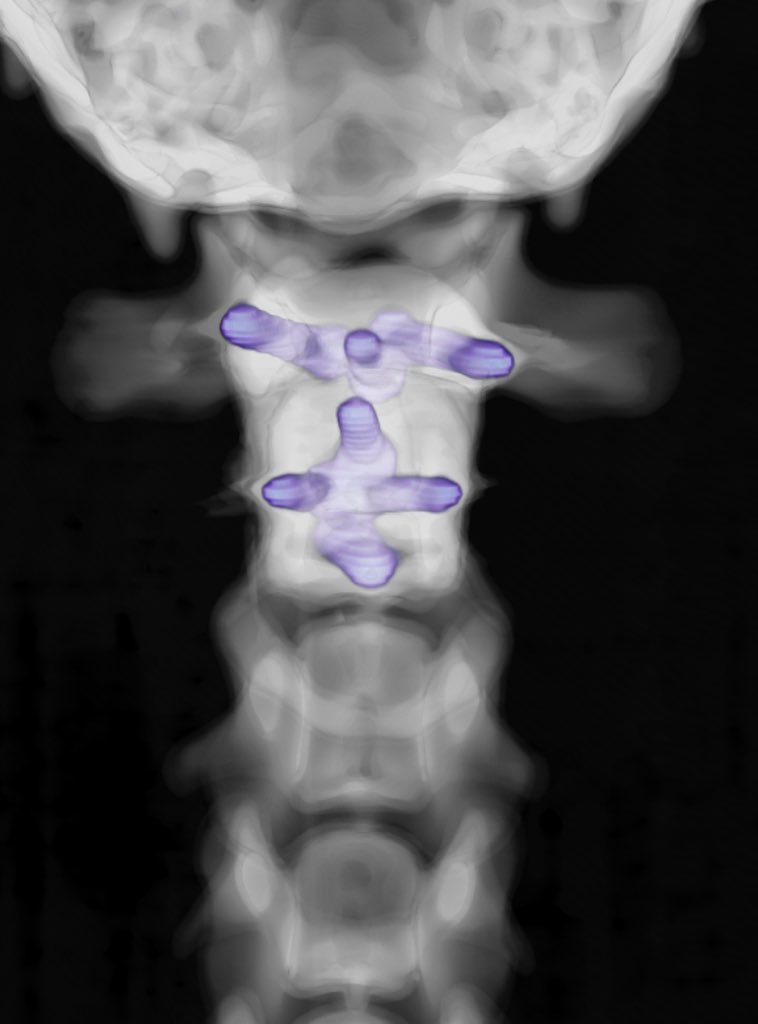

Did you know that baby Frenchies are particularly prone to elbow fractures? Early and accurate repair is essential to restore and maintain a healthy elbow joint 💪🏻 We use custom 3D-printed implants designed specifically for French Bulldogs to optimise repair #mischiefmanaged

Did you know that baby Frenchies are particularly prone to elbow fractures?

Early and accurate repair is essential to restore and maintain a healthy elbow joint 💪🏻

We use custom 3D-printed implants designed specifically for French Bulldogs to optimise repair